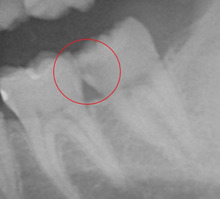

レントゲンを撮影しました。

素人目にはわからないかもしれませんが・・・

赤い丸印内に 黒い影が見えます。

これが もし虫歯です。

レントゲンを撮らなければ 絶対に 見逃します。

隠れ虫歯がありました。